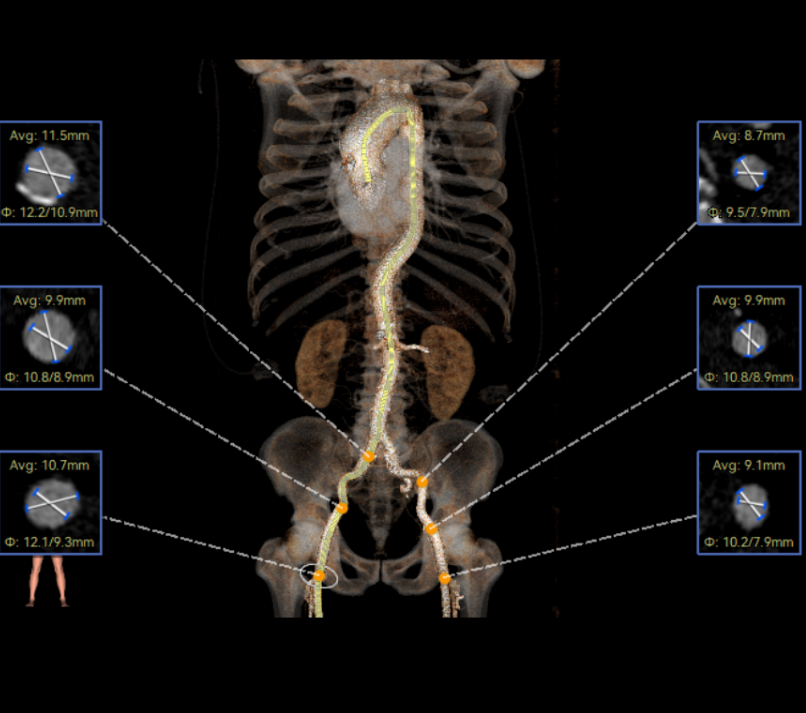

彭小平教授 南昌大学第一附属医院 不断探索医疗可能,筑牢患者长期保障 TAVR 治疗的终极目标,不仅是完成一次手术,更是为患者构建长期稳定的生命保障,而瓣膜耐久性是直接关乎患者后期是否需要二次手术的关键所在。全球首款预装干瓣的问世,为临床提供了全新的选择方案。厂家的15 年质保承诺,是源于材料研发的突破与临床验证的底气。从临床角度,如未来瓣膜可以耐久15年,则可大大减少患者反复就医的身心负担与经济压力,本质上是为患者的长期健康 “投保”。 人生的每一次选择,都需要慎重。相信在行业的前行中,我们不断探索医疗的可能性,让每一次治疗都能真正护航患者长远健康! 患者病史 主诉与现病史:3 年前开始出现胸闷、气促,活动后(如上楼、上坡)症状加重,休息后可缓解,当地医院心脏彩超提示主动脉瓣狭窄,未予特殊治疗;2 年前发现血压轻度升高,口服阿奇沙坦片(40mg,每日 1 次)降压,血压控制尚可;近 1 个月胸闷气促症状明显加重,2025 年 10 月 13 日外院心脏彩超提示主动脉瓣重度狭窄,为进一步诊治入院。 既往史:高血压病史 2 年,规律服用阿奇沙坦片(40mg qd);1 年余前因外伤致腰椎骨折,保守治疗后痊愈;有慢性阻塞性肺疾病病史;有胃窦糜烂、十二指肠球部溃疡史,2023 年曾发生急性上消化道出血;有真菌性食管炎、多发性结肠息肉病史。 术前超声提示:主动脉瓣钙化,主动脉瓣狭窄(重度),左室肥厚,升主动脉增宽。 二尖瓣反流(轻度),三尖瓣反流(轻度),肺动脉瓣高压(轻度)。 左室舒张功能减低,收缩功能正常,左室射血分数 74.7%。 术前CT:Type0型二叶瓣,瓣叶增厚并极重度钙化,钙化主要分布在瓣叶基底部,延伸到左室流出道。主动脉瓣环径24.8mm;升主动脉狭窄后扩张至主动脉弓,双侧瓣叶开口高度可,窦部空间可,STJ内径增宽,升主动脉内径可,预估冠脉低风险;主动脉水平夹角49.1°,非横位心;主动脉弓角、弓距可;“自杀左室”,建议术前补液,ECMO湿备,术中注意循环崩溃。 外周双侧入路内径可,髂总动脉有零星散状钙化,双侧股动脉均能通过20F大鞘,右股低分叉。 手术策略:推荐使用右侧股动脉为主入路,左侧股动脉为辅助入路;右股分叉上方1cm穿刺;推荐使用18mm球囊预扩,预装AV23瓣膜。 手术过程:在右股动脉穿刺建立通路后,顺利送入大鞘,经食道超声及血管造影确认路径稳定。18mm球囊预扩后评估冠脉灌注良好,后将Prostyle A® AV23瓣膜精准释放于目标位置,20mm球囊后扩,超声显示轻微瓣周漏,术后即刻造影显示无明显反流,峰值压差由术前的80mmHg降至12mmHg,心功能明显改善,患者生命体征平稳。 18球囊预扩无腰无漏 输送器跨瓣顺利 定位 平稳释放瓣膜 20球囊后扩 最终造影,位置良好,轻微瓣周漏 Prostyle A®预装干瓣——助力临床最优化解决方案 1、流入端桶状设计:流入端桶状的设计,锚定迅速,有效减少释放步骤,提升植入稳定性; 2、平衡的收腰设计:二叶瓣小心室患者对瓣膜径向支撑力提出更高要求,Prostyle A®均衡的收腰设计可更好适应小瓣环及不规则瓣口结构,保证了EOA,有效降低了循环崩溃风险,提高瓣膜的耐久性; 3、预装干瓣 便捷顺安:金仕生物专利抗钙化技术运用纳米技术去除组织内的细胞碎片和磷脂,封闭游离醛基,从根本上阻断了瓣膜钙化的多项因素,显著提升了瓣膜的耐久性;同时,相比较传统戊二醛保存方式,干式存储最大限度的保留心包的亲水亲油平衡,还原组织天然曲柔性,进一步保障了瓣叶开合,保证长期耐久性; 专家简介 彭小平 南昌大学第一附属医院(点击查看专家详细简历) · END ·